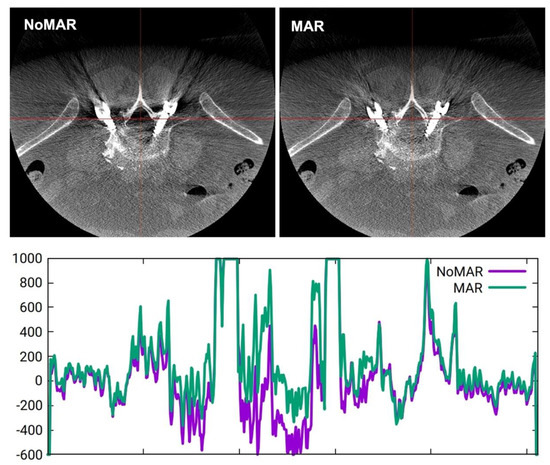

2.3. Image Analysis